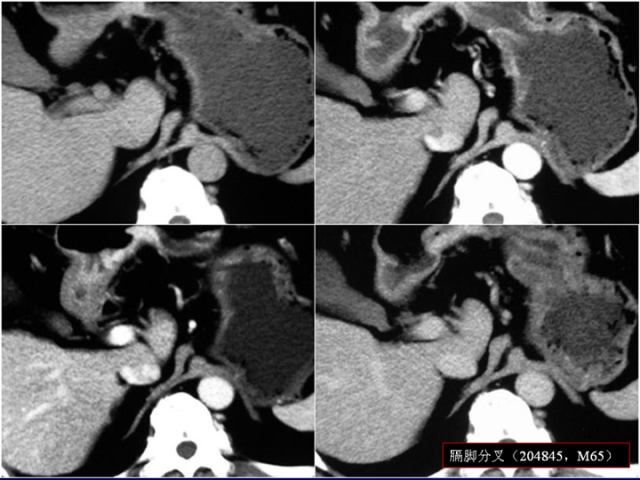

膈肌角解剖及常见变异

作者:王俭 上海长征医院